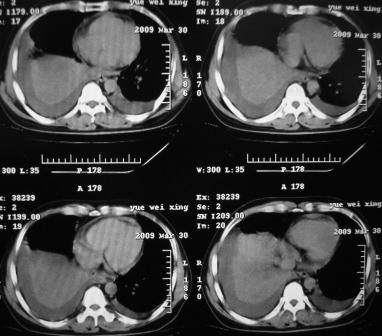

xx 男 43岁

右肺下叶支气管中断闭塞,右下肺见不规块影,并胸腔积液,考虑肺中央型肺癌继发下叶不张,\\双侧胸腔积液,心包积液。

右侧中央型肺癌伴右肺下叶不张,双肺及纵隔淋巴转移,双侧胸腔积液,心包积液。

1)考虑右侧中央型肺癌伴右肺下叶不张,双肺及纵隔淋巴转移。2)双侧胸腔积液,以右侧为甚。3)心包积液。

考虑右侧中央型肺癌伴右肺下叶不张,双肺及纵隔淋巴转移,双侧胸腔积液。不除外结核。

考虑右肺下叶中心性肺癌并纵隔淋巴结、双肺转移伴右肺下叶阻塞性肺不张;双侧胸水,右侧为著;心包积液